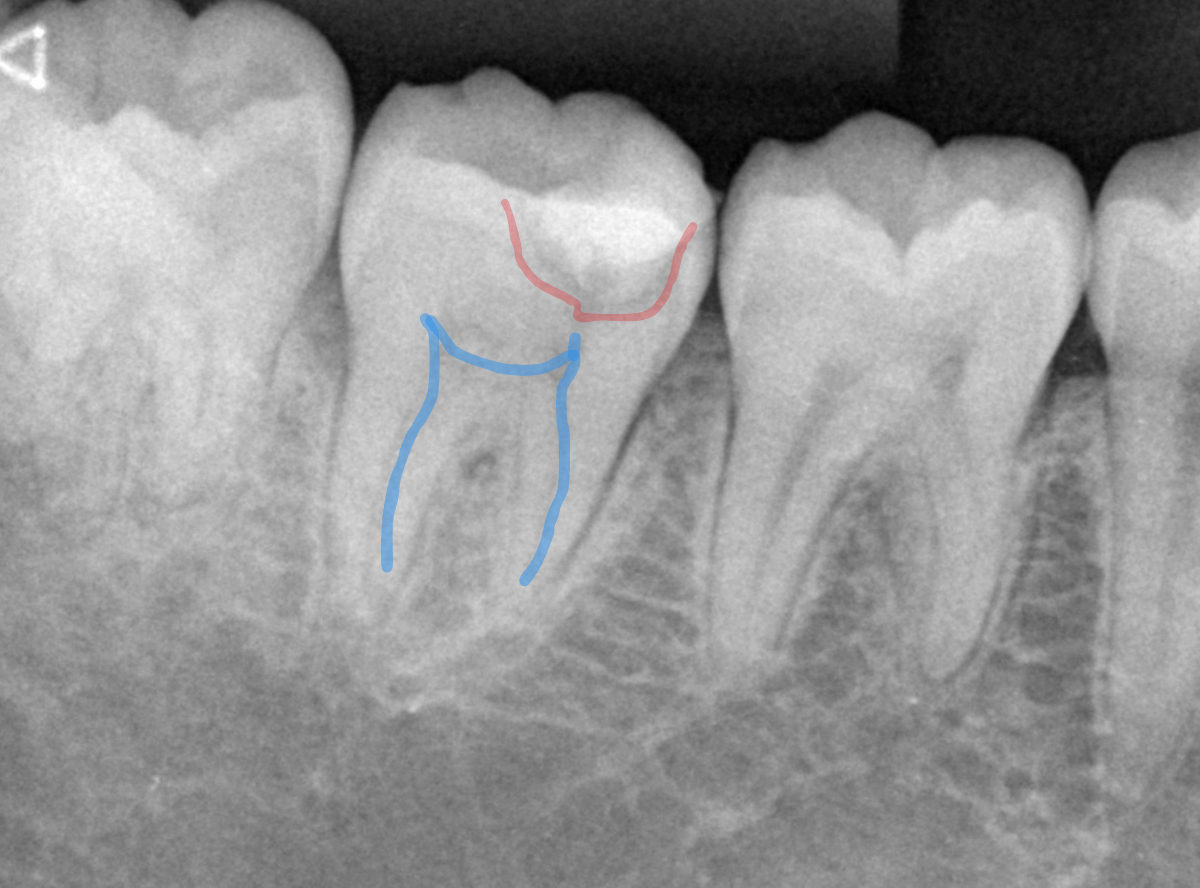

レントゲン写真で確認します。

青い線が歯の神経です。

赤い線が虫歯と思われる部分です。

思った通り、神経に達してしまいそうな大きな虫歯です。

患者さんには、神経を取る治療が必要な可能性が高い事を説明します。